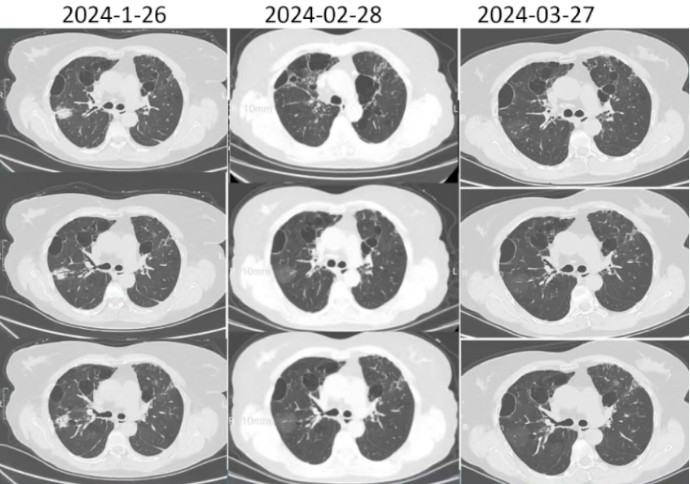

【出院后1个月】2024年2月28日,查CRP 34.42 mg/L。胸部CT(图3):胸廓基本对称,双肺内片见状及网格样高密度影,右肺部分病变较前密度减低,各主支气管开口通畅,双肺内示散在低密度影;纵隔内未见明显肿大淋巴结,前纵隔内示约0.9 cm×0.5 cm结节影,边界清晰,密度均匀。

图片

3  患者随诊胸部CT与之前对比

【出院后2个月】2024年3月27日,CRP 2.04 mg/L。胸部CT(图4):胸廓基本对称,双肺网格样高密度影,双肺内散在低密度影;各主支气管开口通畅,纵隔内未见明显肿大淋巴结,前纵隔内示约0.9 cm×0.5 cm结节影,边界清晰,密度均匀。嘱继续口服艾沙康唑治疗。

4  患者随诊胸部CT对比